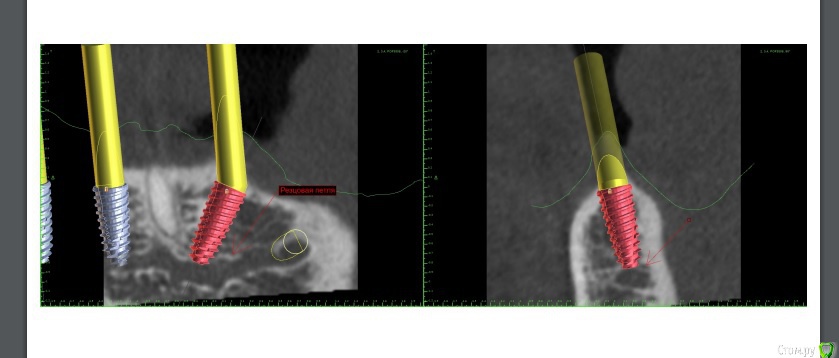

Dman Опубликовано 22 августа, 2019 Поделиться Опубликовано 22 августа, 2019 (изменено) Всем привет. Закончил кейс, который продвигался очень сложно всю дорогу, делюсь)Пациент 70 лет. Состояние здоровья соответствующее. Во рту так Слепки, кт, планирование, изготовление шаблона, изначально хотел идти на оллинфо, проектировщик шаблона долго не хотел делать под дистальные имланты длину 4*13(очень широкая резцовая петля). Уговорил, шаблон готов, поехали.Сверлится очень плохо, несмотря на просьбу добавить пару фиксирующих пинов их нет, да и места куда их там уместить не особо. В итоге из 4 пилотных 3 мимо. раскрываюсь, редукция, поднялось давление 160, при редукции бьют фонтанчики из сосудов в области центральных резцов, периодически коагулирую их лазером. Засверливаюсь дистально ии! льет кровища как из шланга. Меняю план, ставлю дистально 4*8,5. Ушиваюсь. Панорама Сразу слепок, протез уже готов под нагрузку, техник готовит протез.Вид на следующий день Перебазировываю во рту, прикручиваю. Панорама На этом все, вторая часть в ортопедическом разделе. Буду рад услышать советы. Изменено 22 августа, 2019 пользователем Dman 7 Ссылка на комментарий

pit Опубликовано 30 августа, 2019 Поделиться Опубликовано 30 августа, 2019 Всем привет. Закончил кейс, который продвигался очень сложно всю дорогу, делюсь)Пациент 70 лет. Состояние здоровья соответствующее. Во рту так Сверлится очень плохо, несмотря на просьбу добавить пару фиксирующих пинов их нет, да и места куда их там уместить не особо. В итоге из 4 пилотных 3 мимо. раскрываюсь, редукция, поднялось давление 160, при редукции бьют фонтанчики из сосудов в области центральных резцов, периодически коагулирую их лазером. Засверливаюсь дистально ии! льет кровища как из шланга. Меняю план, ставлю дистально 4*8,5. На этом все, вторая часть в ортопедическом разделе. Буду рад услышать советы. 1. Я не совсем понимаю почему нельзя было установить 4х11,5 или 4х13, если установлены 4х8,5??? Кровоточивость не мешает сверлению, вопрос всего в 3-4 мм.2. Дистальные импланты надо было установить на 5 мм дистальнее, судя по ОПТГ. Для этого нужно было откинуть лоскуты и выделить оба ментальных нерва.3. В клинике всегда нужно иметь нифедипин, 20 мг под язык - экстренная помощь при резком повышении АД. Хотя 160 не такая высокая цифра, чтобы говорить о ужасном кровотечении при типовой операции4. Фонтанчики крови часто бывают при редукции и при нормальном давлении. С ними лучше всего бороться алмазным шариком на больших оборотах без воды или локальным сдавлением кости щипцами.5. В конце концов можно было остановить операцию, назначить а/б, гипотензивные препараты, режим и через 2-3 дня все доустановить.6. Отвечу здесь по ортопедии. Даже в Вашем решении можно было выполнить несъемную конструкцию. из 12-и зубов с компромиссными молярами, длина имплантов имеет решающее значение только при немедленной нагрузке. Ссылка на комментарий

Dman Опубликовано 30 августа, 2019 Автор Поделиться Опубликовано 30 августа, 2019 1. Я не совсем понимаю почему нельзя было установить 4х11,5 или 4х13, если установлены 4х8,5??? Кровоточивость не мешает сверлению, вопрос всего в 3-4 мм.2. Дистальные импланты надо было установить на 5 мм дистальнее, судя по ОПТГ. Для этого нужно было откинуть лоскуты и выделить оба ментальных нерва.3. В клинике всегда нужно иметь нифедипин, 20 мг под язык - экстренная помощь при резком повышении АД. Хотя 160 не такая высокая цифра, чтобы говорить о ужасном кровотечении при типовой операции4. Фонтанчики крови часто бывают при редукции и при нормальном давлении. С ними лучше всего бороться алмазным шариком на больших оборотах без воды или локальным сдавлением кости щипцами.5. В конце концов можно было остановить операцию, назначить а/б, гипотензивные препараты, режим и через 2-3 дня все доустановить.6. Отвечу здесь по ортопедии. Даже в Вашем решении можно было выполнить несъемную конструкцию. из 12-и зубов с компромиссными молярами, длина имплантов имеет решающее значение только при немедленной нагрузке. 1 лило реально как из шланга, + там резцовая петля очень широкая думаете можно было оставить верхушку импланта в ней, или пройти насквозь?2 найду кт гляну, но планировал не один, видимо были причины3 не слышал про такой, найдем и купим4 первая объемная редукция, ранее не слышал что это норма(5 не думал что получится что-то лучше, в связи с резцовой петлей6 за неимением опыта(копылов давал данные что дистальные меньше 11мм, неблагоприятный прогноз), решил перестраховаться, возможно неправ огромное спасибо за советы, будем расти Ссылка на комментарий